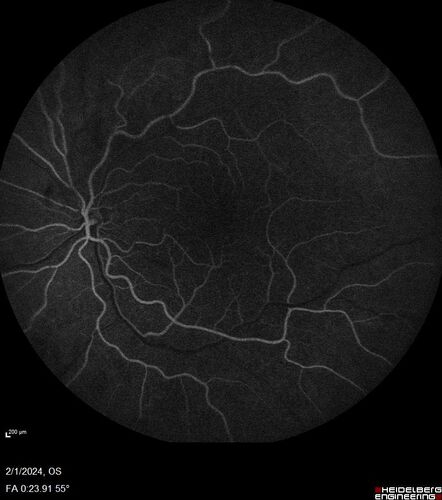

71 year old female with 3 months of vision loss and not feeling well.  She has been bruising on her legs.  Her vision was 20/100 in each eye with macular edema.  She was treated with Avastin and her CBC was checked.  She had a WBC of 267 thousand and was diagnosed with CML.

leukemia_118545_14.jpg leukemia_118545_15.jpg leukemia_118545_16.jpg leukemia_118545_17.jpg leukemia_118545_18.jpg